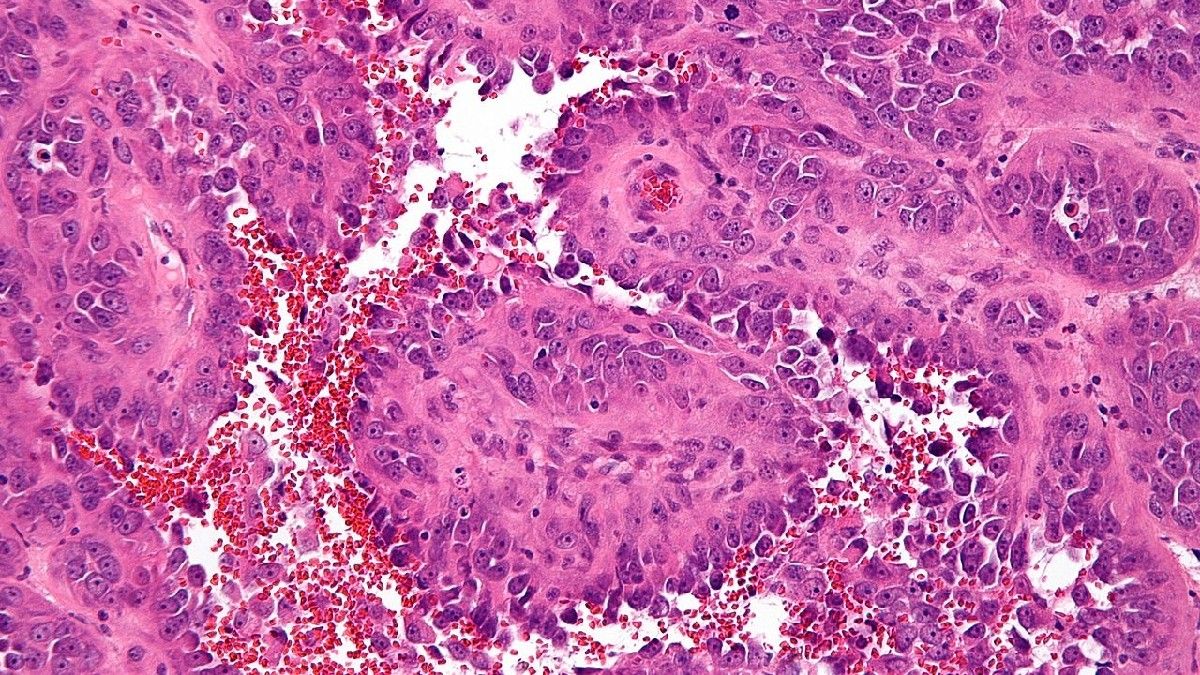

Angiosarkoma sendiri merupakan jenis kanker langka yang berkembang di lapisan pembuluh darah dan pembuluh getah bening atau limfe. Penyebarannya dapat menjangkiti bagian tubuh mana pun, namun seringnya kanker angiosarkoma menyerang bagian kulit di kepala dan leher.

Angiosarkoma berkembang karena sel di lapisan pembuluh darah dan pembuluh getah bening bermutasi dan membelah diri secara tidak normal. Pada gilirannya, sel-sel kanker angiosarkoma pecah dan menyebar ke bagian tubuh lainnya.